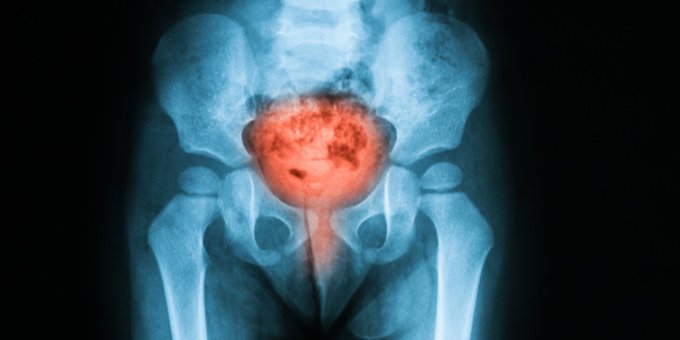

La mayoría de las infecciones urinarias son causadas por bacterias que ingresan a la uretra y llegan hasta a la vejiga. Entérate aquí sobre cuidados personales para mujeres con infecciones urinarias ow.ly/sNXB50BpUN4